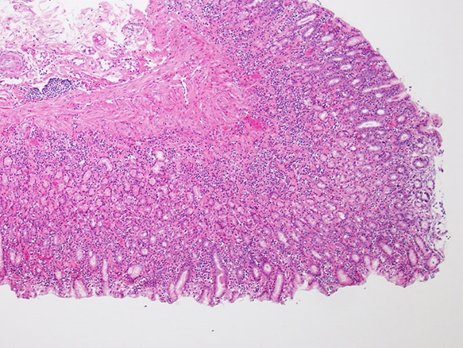

好酸球性胃腸炎 (Eosinophilic Gastroenteritis, EGE): LPEと比較して稀な形態ですが、一般に重度な臨床経過を辿ることが知られています 。組織学的に中等度から多数の好酸球が胃腸管壁に浸潤している場合に、「好酸球性胃腸炎」という診断名が与えられます。特にEGEは若齢の雄で多く見られるという疫学的報告があり 、臨床徴候には、慢性または間欠性の下痢(粘液や新鮮血を伴うこともある)、嘔吐(重症例では噴出性のこともある)、体重減少、食欲不振、および元気消失などが含まれます 。身体検査では、腸管ループの触知可能な肥厚や、腹腔内リンパ節の腫大が認められることがあります 。病理学的な所見として、EGEにおける好酸球の浸潤は、粘膜層に限定されず、粘膜下層、筋層、さらには漿膜に至るまで、腸管壁の深部構造全体に及ぶことが顕微鏡画像で示されています 。このような広範囲にわたる浸潤が、重度の嘔吐や腸管の肥厚といった臨床症状の原因となります〔Hoefer et al.2014〕。

最終的には胃腸の外科的生検による病理組織学的検査で鑑別が行われます〔Lennox 2005〕。